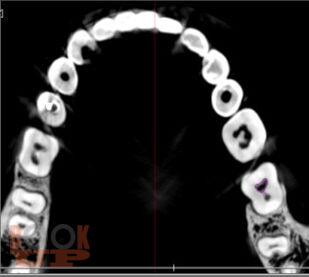

Учебное пособие предназначено для студентов стоматологического факультета, врачей-ординаторов и стоматологов практического здравоохранения. Содержит информацию о внедрении компьютерных программ в эндодонтии, которые позволяют моделировать клинические ситуации в рамках виртуального пространства, что дает возможность заблаговременно предотвращать ошибки и осложнения, оценивать эффективность лечения, прогнозировать отдаленные результаты.